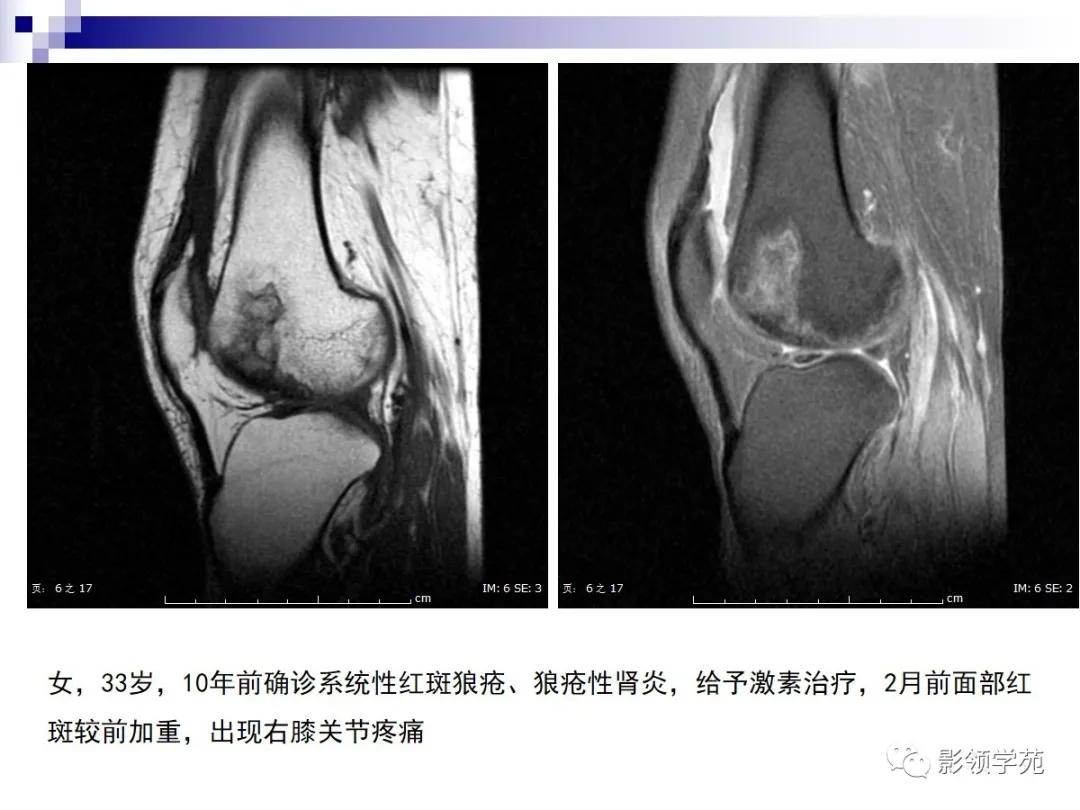

病例2:女性,45岁,病史:临床诊断SLE10年,膝关节疼痛4年。